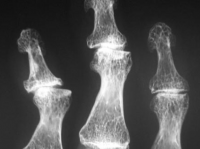

A osteoartrite, também conhecida como doença articular degenerativa, é um processo de deterioração progressiva da cartilagem articular e formação de osso novo (osteófitos) com a superfície articular. A osteoartrose primária está relacionada com a idade e associada a estresse mecânico. A osteoartrite secundária é devido a uma causa subjacente, como trauma, inflamatórias, metabólicas ou a doença do tecido conjuntivo. As características da doença são bem ilustradas nas mãos de adultos com osteoartrose nas figuras abaixo.